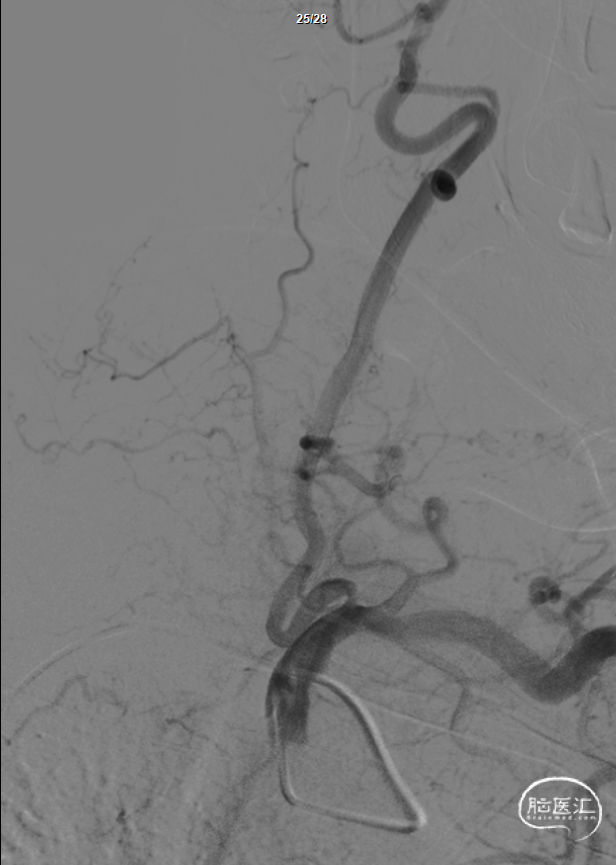

造影结果:

1.右侧桡动脉入路,造影显示:II型主动脉弓,左侧椎动脉V1段走形迂曲,起始部重度狭窄,狭窄率约为75%。

2.患者经桡动脉入路后,减少术后卧床问题,及有效减少穿刺点血肿,假性动脉瘤等并发症。